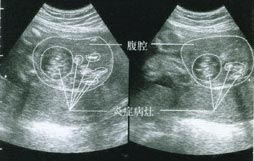

3、腹脹與腹水多數患者有腹脹感,可因結核病中毒症狀或腹膜炎伴有的腸功能紊亂引起。約有三分之一患者可

出現腹水,以小量、中等量為多見。腹水量超出1000ml時可發現移動性濁音。少量腹水需藉助B超檢查。